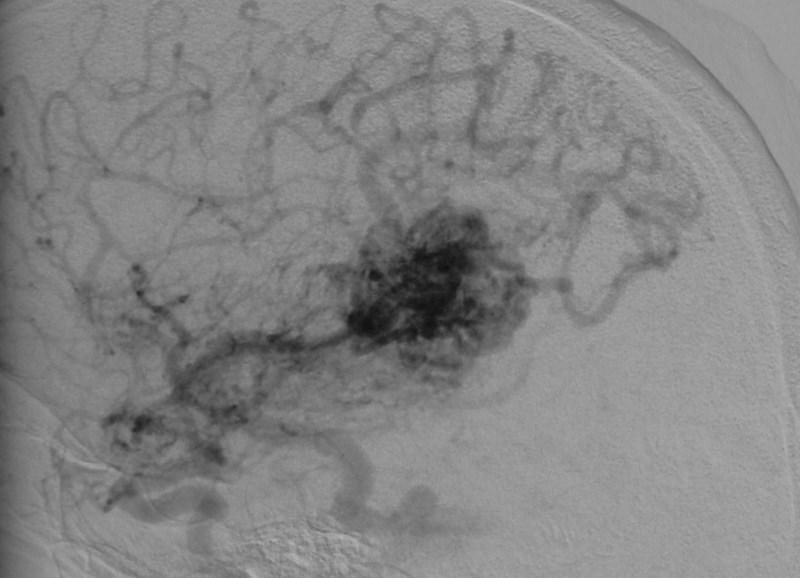

Arteriovenous malformations

Arteriovenous malformations of the brain are abnormal bunch of blood vessels that can rupture causing bleeding, or may cause seizures. Brain imaging (CT, MRI) is required for early diagnosis, while definitive treatment is carried out after cerebral angiography. Treatment implies craniotomy and excision of the AVM, which can be done safely in majority of the cases. Embolisation and radiosurgery are acceptable substitutes, but carry risk of further bleeding.